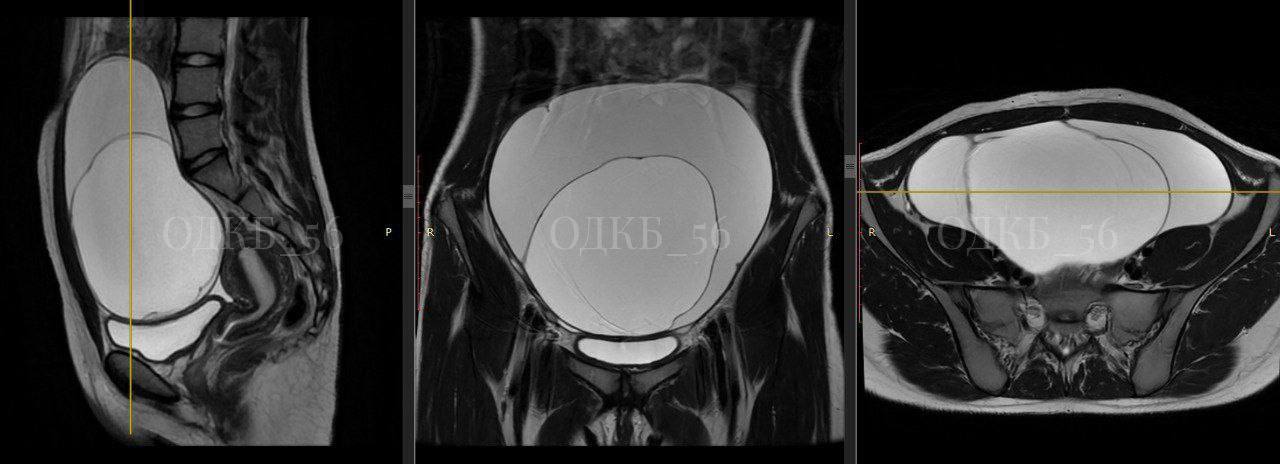

UTV | Оренбург

Оренбургские врачи удалили 20 сантиметровую опухоль яичника у 14 летней девочки Хирурги Областной детской клинической больницы успешно провели сложную операцию по удалению крупной муцинозной цистаденомы яичника у подростка Пациентка поступила в больницу с экстренными болями в животе где обследование выявило огромное образование размером 20 см Из за размеров опухоли у врачей были подозрения на онкологию Однако срочно проведенная операция и последующее гистологическое исследование показали что опухоль доброкачественная Девочка была выписана спустя неделю Подписывайся на UTV Оренбуржье